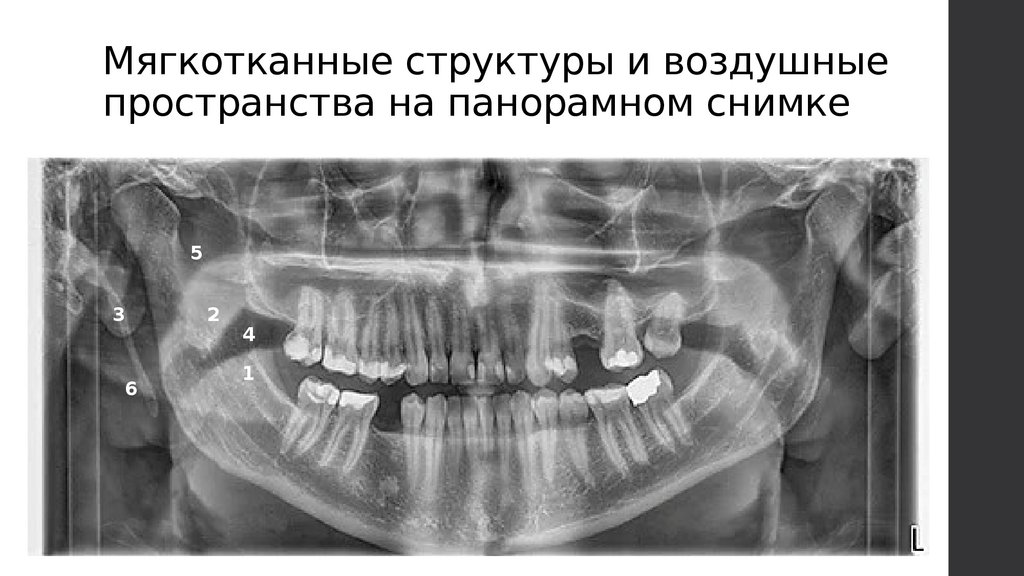

Мягкотканные структуры и воздушные

пространства на панорамном снимке

5

3

6

2

4

1